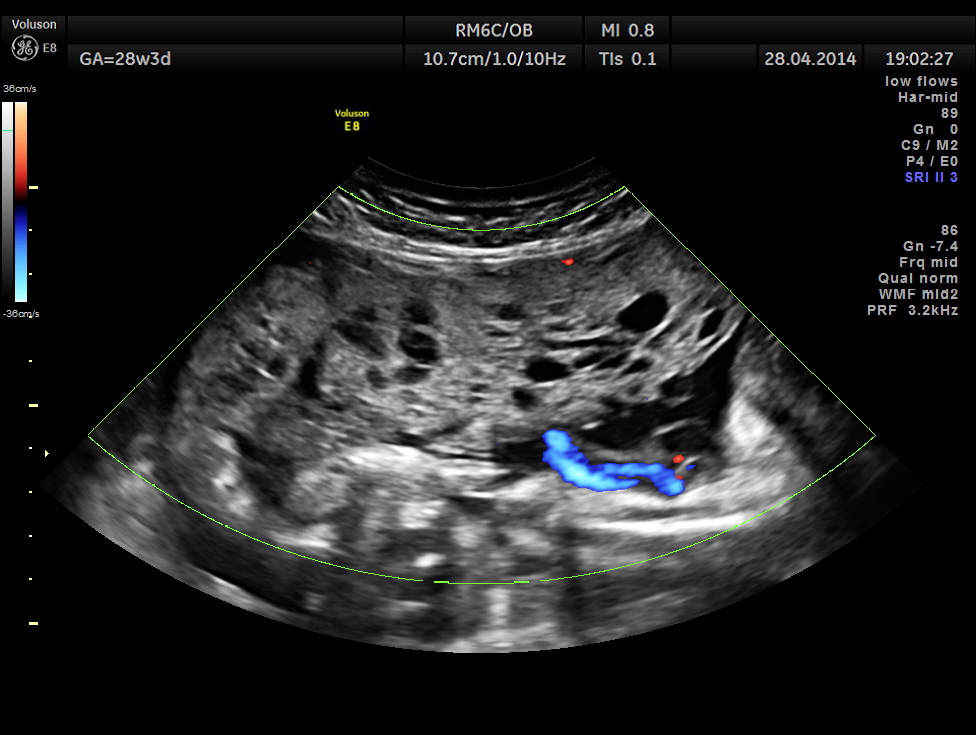

She came again after 2 months .The placenta appeared nearly the same , but showed more vascularity.

The spectral Doppler pictures are given below

Umbilical artery R.I . AND P.I. appear to be normal now. The cerebro placental ratio is also normal.